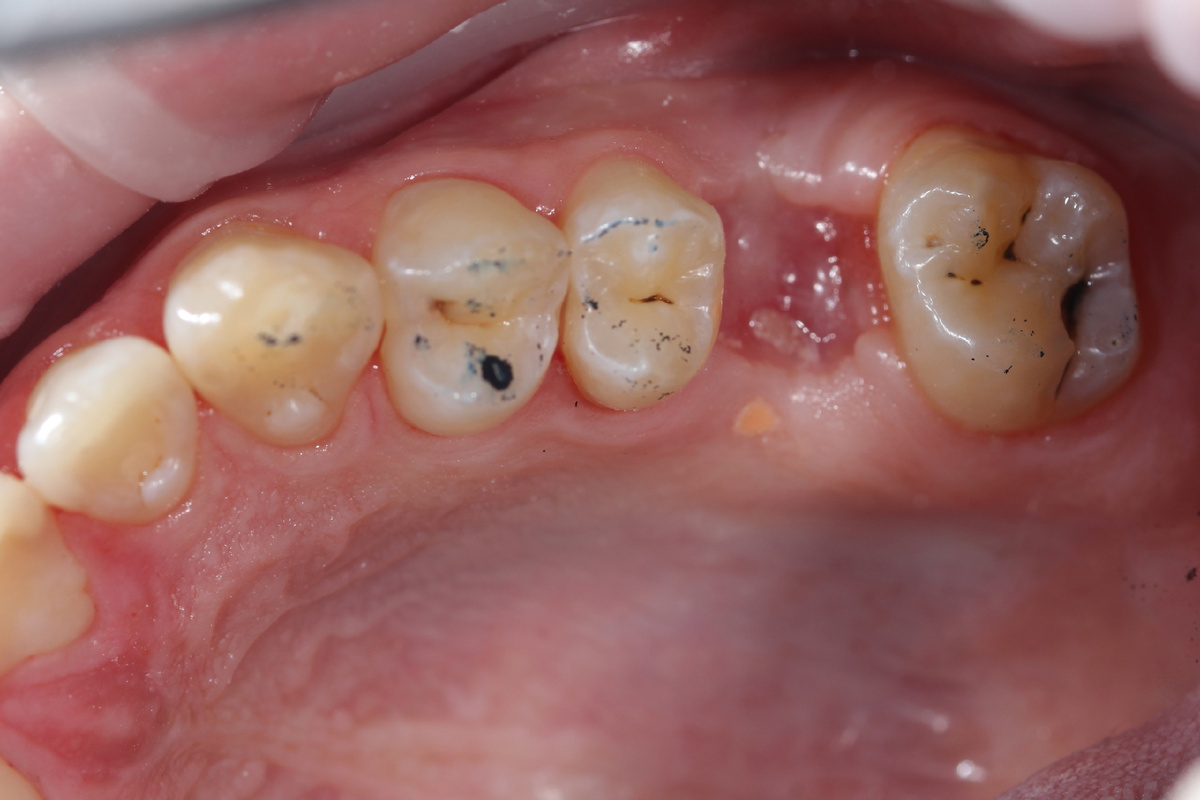

В этом случае пациент обратился с кариозными поражениями на верхней челюсти, и всего за 5 часов мы восстановили 12, 13, 14, 15 и 17 зубы.

🔹Тщательная диагностика — с помощью микроскопа мы выявили даже скрытые кариозные поражения, которые не всегда видны невооружённым глазом.

🔹Лечение проводилось с использованием коффердама, что обеспечило высокую точность.

🔹 Удалили поврежденные ткани и восстановили зубы с максимальной анатомической точностью.

🔹 На фотографиях вы можете увидеть результат лечения — зубы восстановлены естественно и анатомически верно, в результате чего потребовались минимальные корректировки по прикусу.